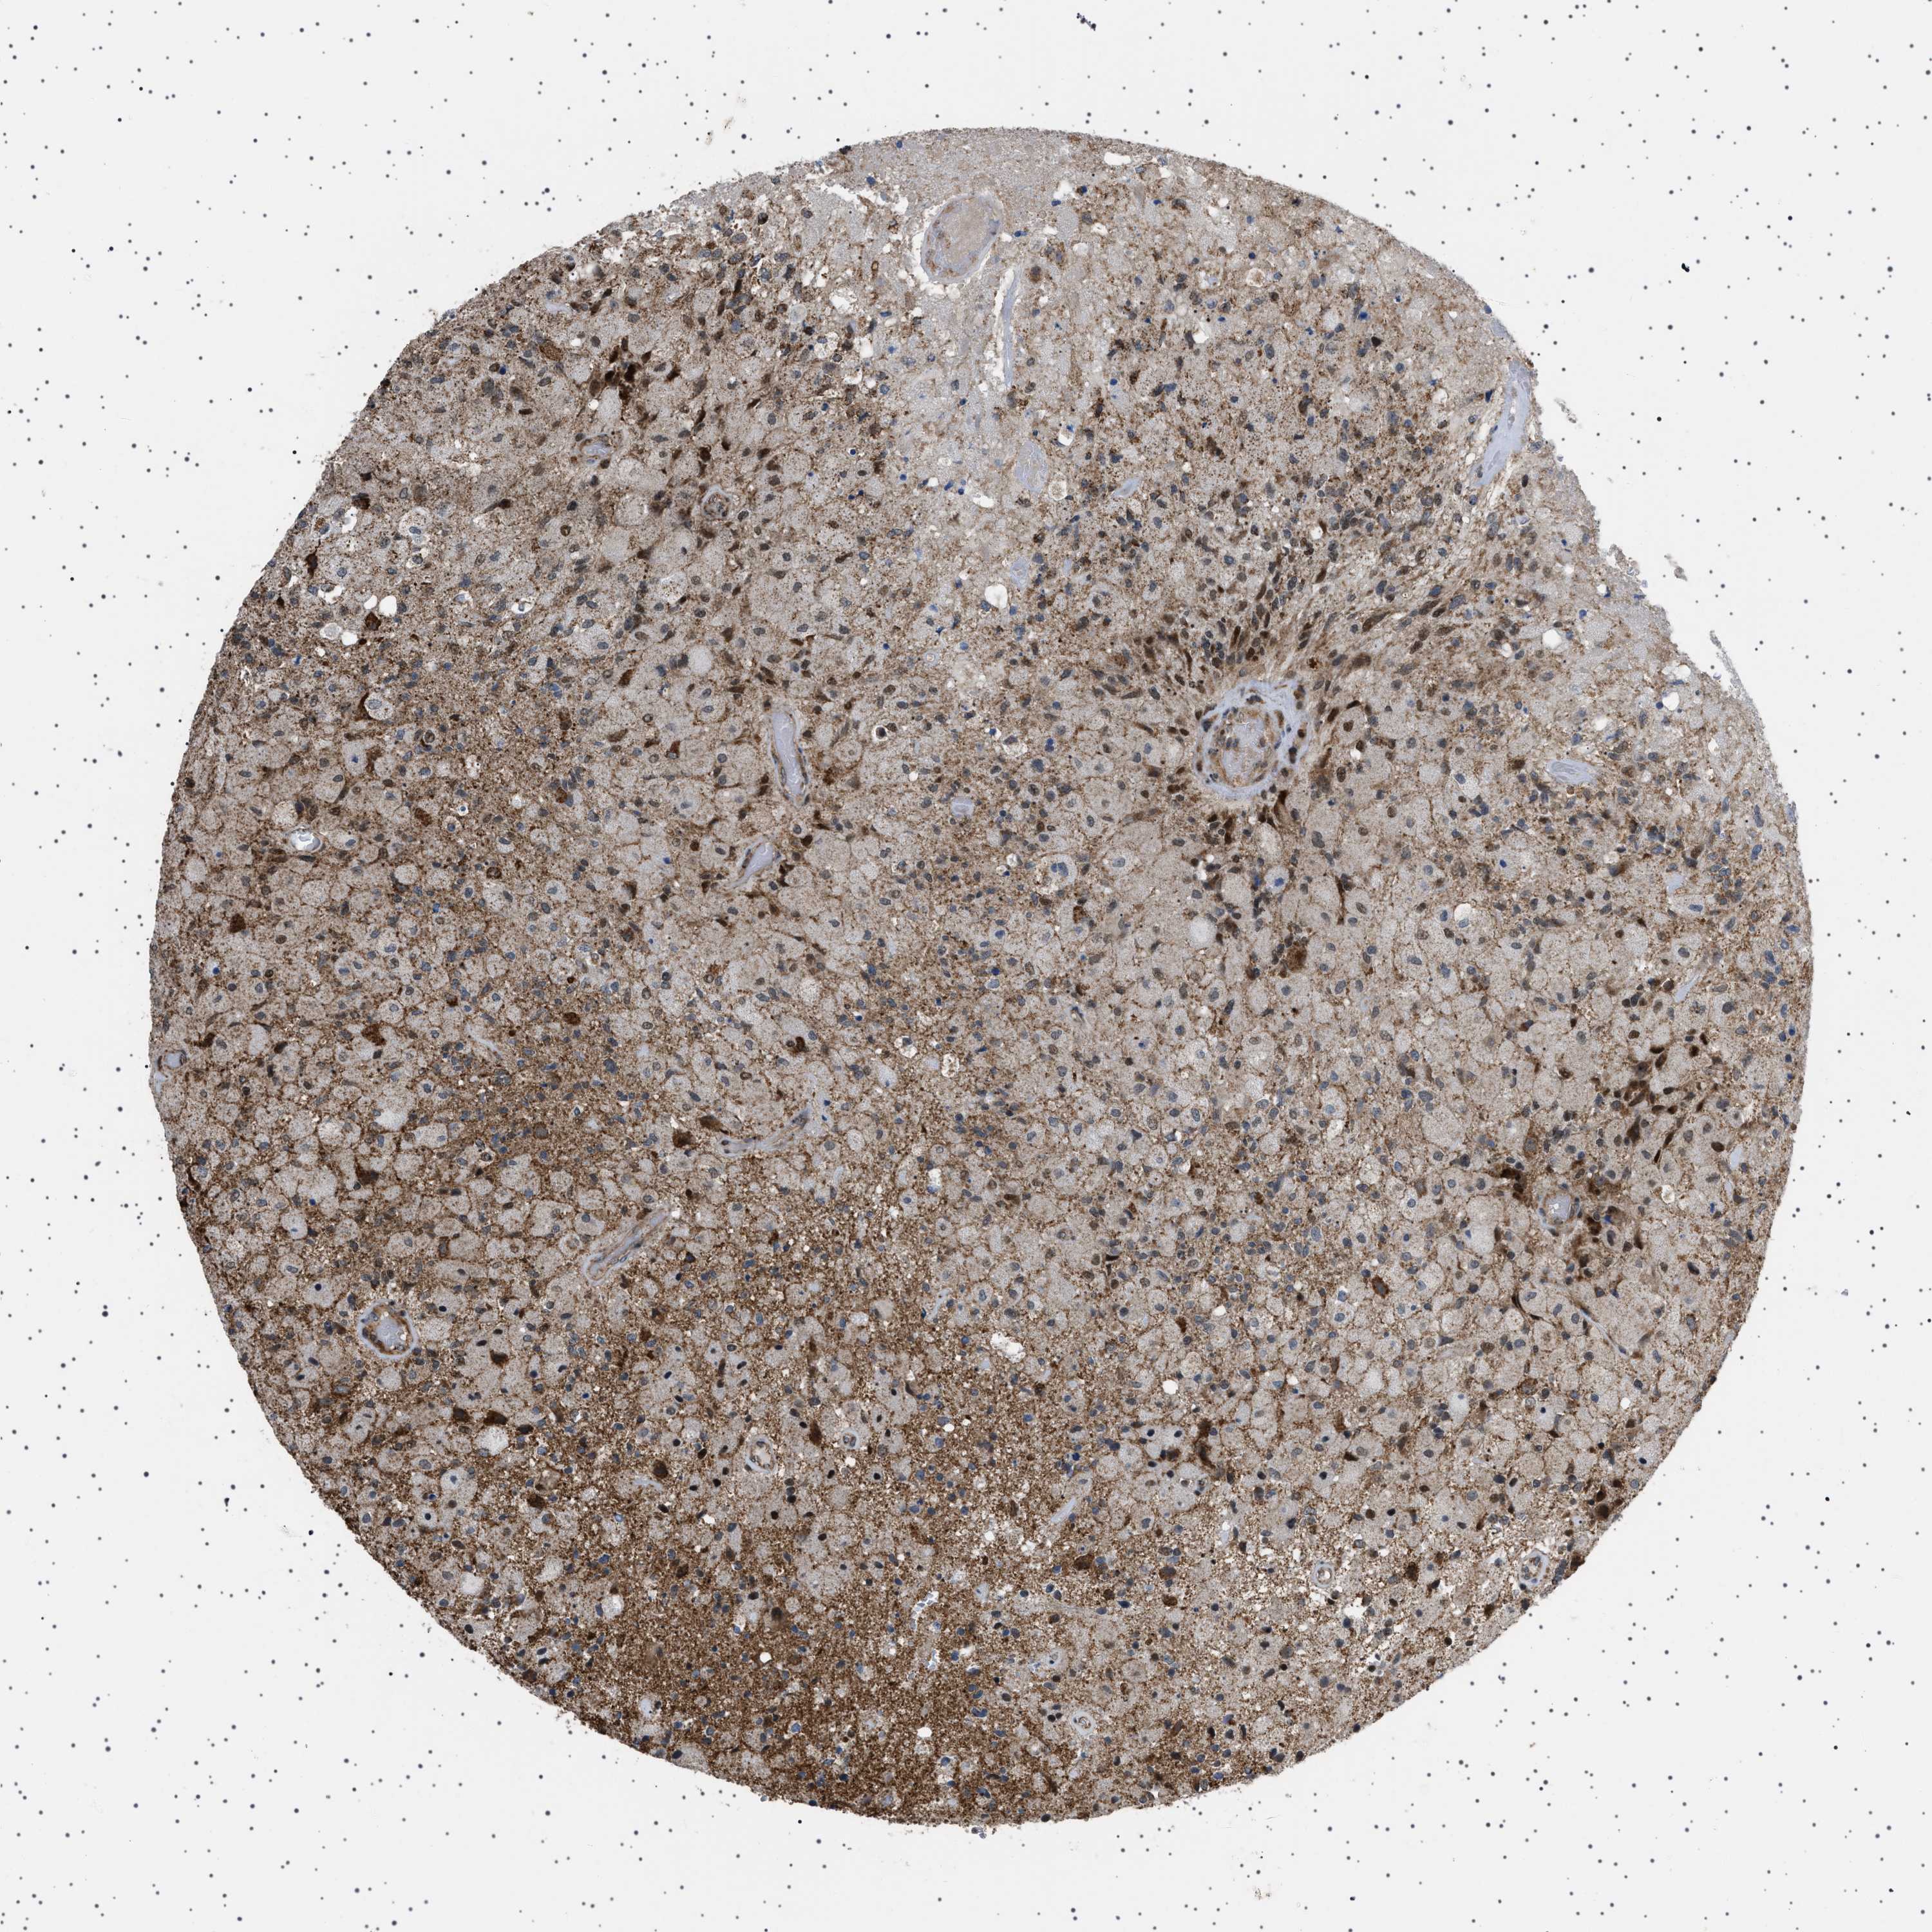

GLIOMA - Protein expressioni

A mouse-over function shows sample information and annotation data. Click on an image to view it in a full screen mode. Samples can be filtered based on level of antibody staining by selecting one or several of the following categories: high, medium, low and not detected. The assay and annotation is described here.

Note that samples used for immunohistochemistry by the Human Protein Atlas do not correspond to samples in the TCGA dataset.

Antibody stainingi

Antibody staining in the annotated cell types in the current human tissue is reported as not detected, low, medium, or high, based on conventional immunohistochemistry profiling in selected tissues. This score is based on the combination of the staining intensity and fraction of stained cells.

Each image is clickable and will lead to virtual microscopy that enables deeper exploration of all samples and also displays staining intensity scores, fraction scores and subcellular localization as well as patient and tissue information for each sample.

Antibody HPA017214

Staining

High

Medium

Low

Not detected

Intensity

Strong

Moderate

Weak

Negative

Quantity

>75%

75%-25%

<25%

None

Location

Nuclear

Cytoplasmic/membranous

Cytoplasmic/membranous,nuclear

Glioma, malignant, High grade

Glioma, malignant, Low grade